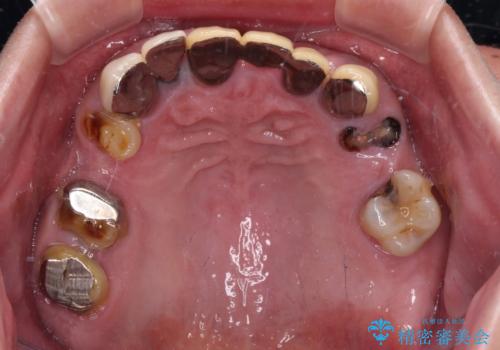

- 奥歯の欠損や、ボロボロになった歯を気にして来院された患者様です。

転勤で東京にいる1年間の間に治療を終えたいとのことで、奥歯のインプラント埋入や前歯部の歯周外科処置など、治癒に時間を要するものから始めていき、治癒期間に根管治療や補綴治療を進めて行くこととしました。

インプラントにより奥歯の咬み合わせが安定し、上顎前歯の歯肉ラインを調整するための骨外科処置により深く咬みこんでいた前歯部も負担のかからない咬み合わせに改善することができました。